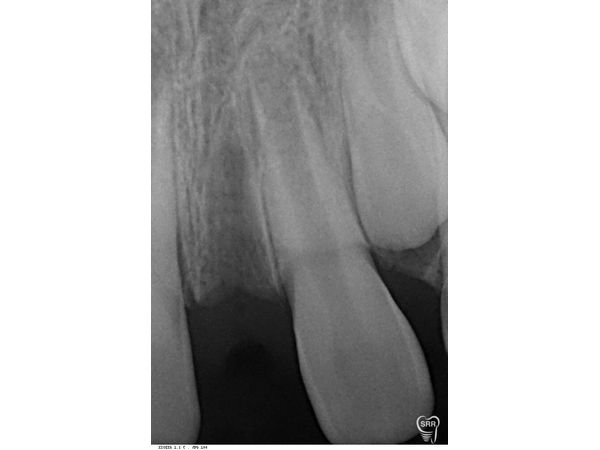

При осмотре на 15-й день после удаления лунка зажила с образованием рубца. В области удаления слизистая оболочка была в нормальном состоянии. Прощупывание безболезненно.

Удаление прошло успешно. Пациент продолжил ортодонтическое лечение.